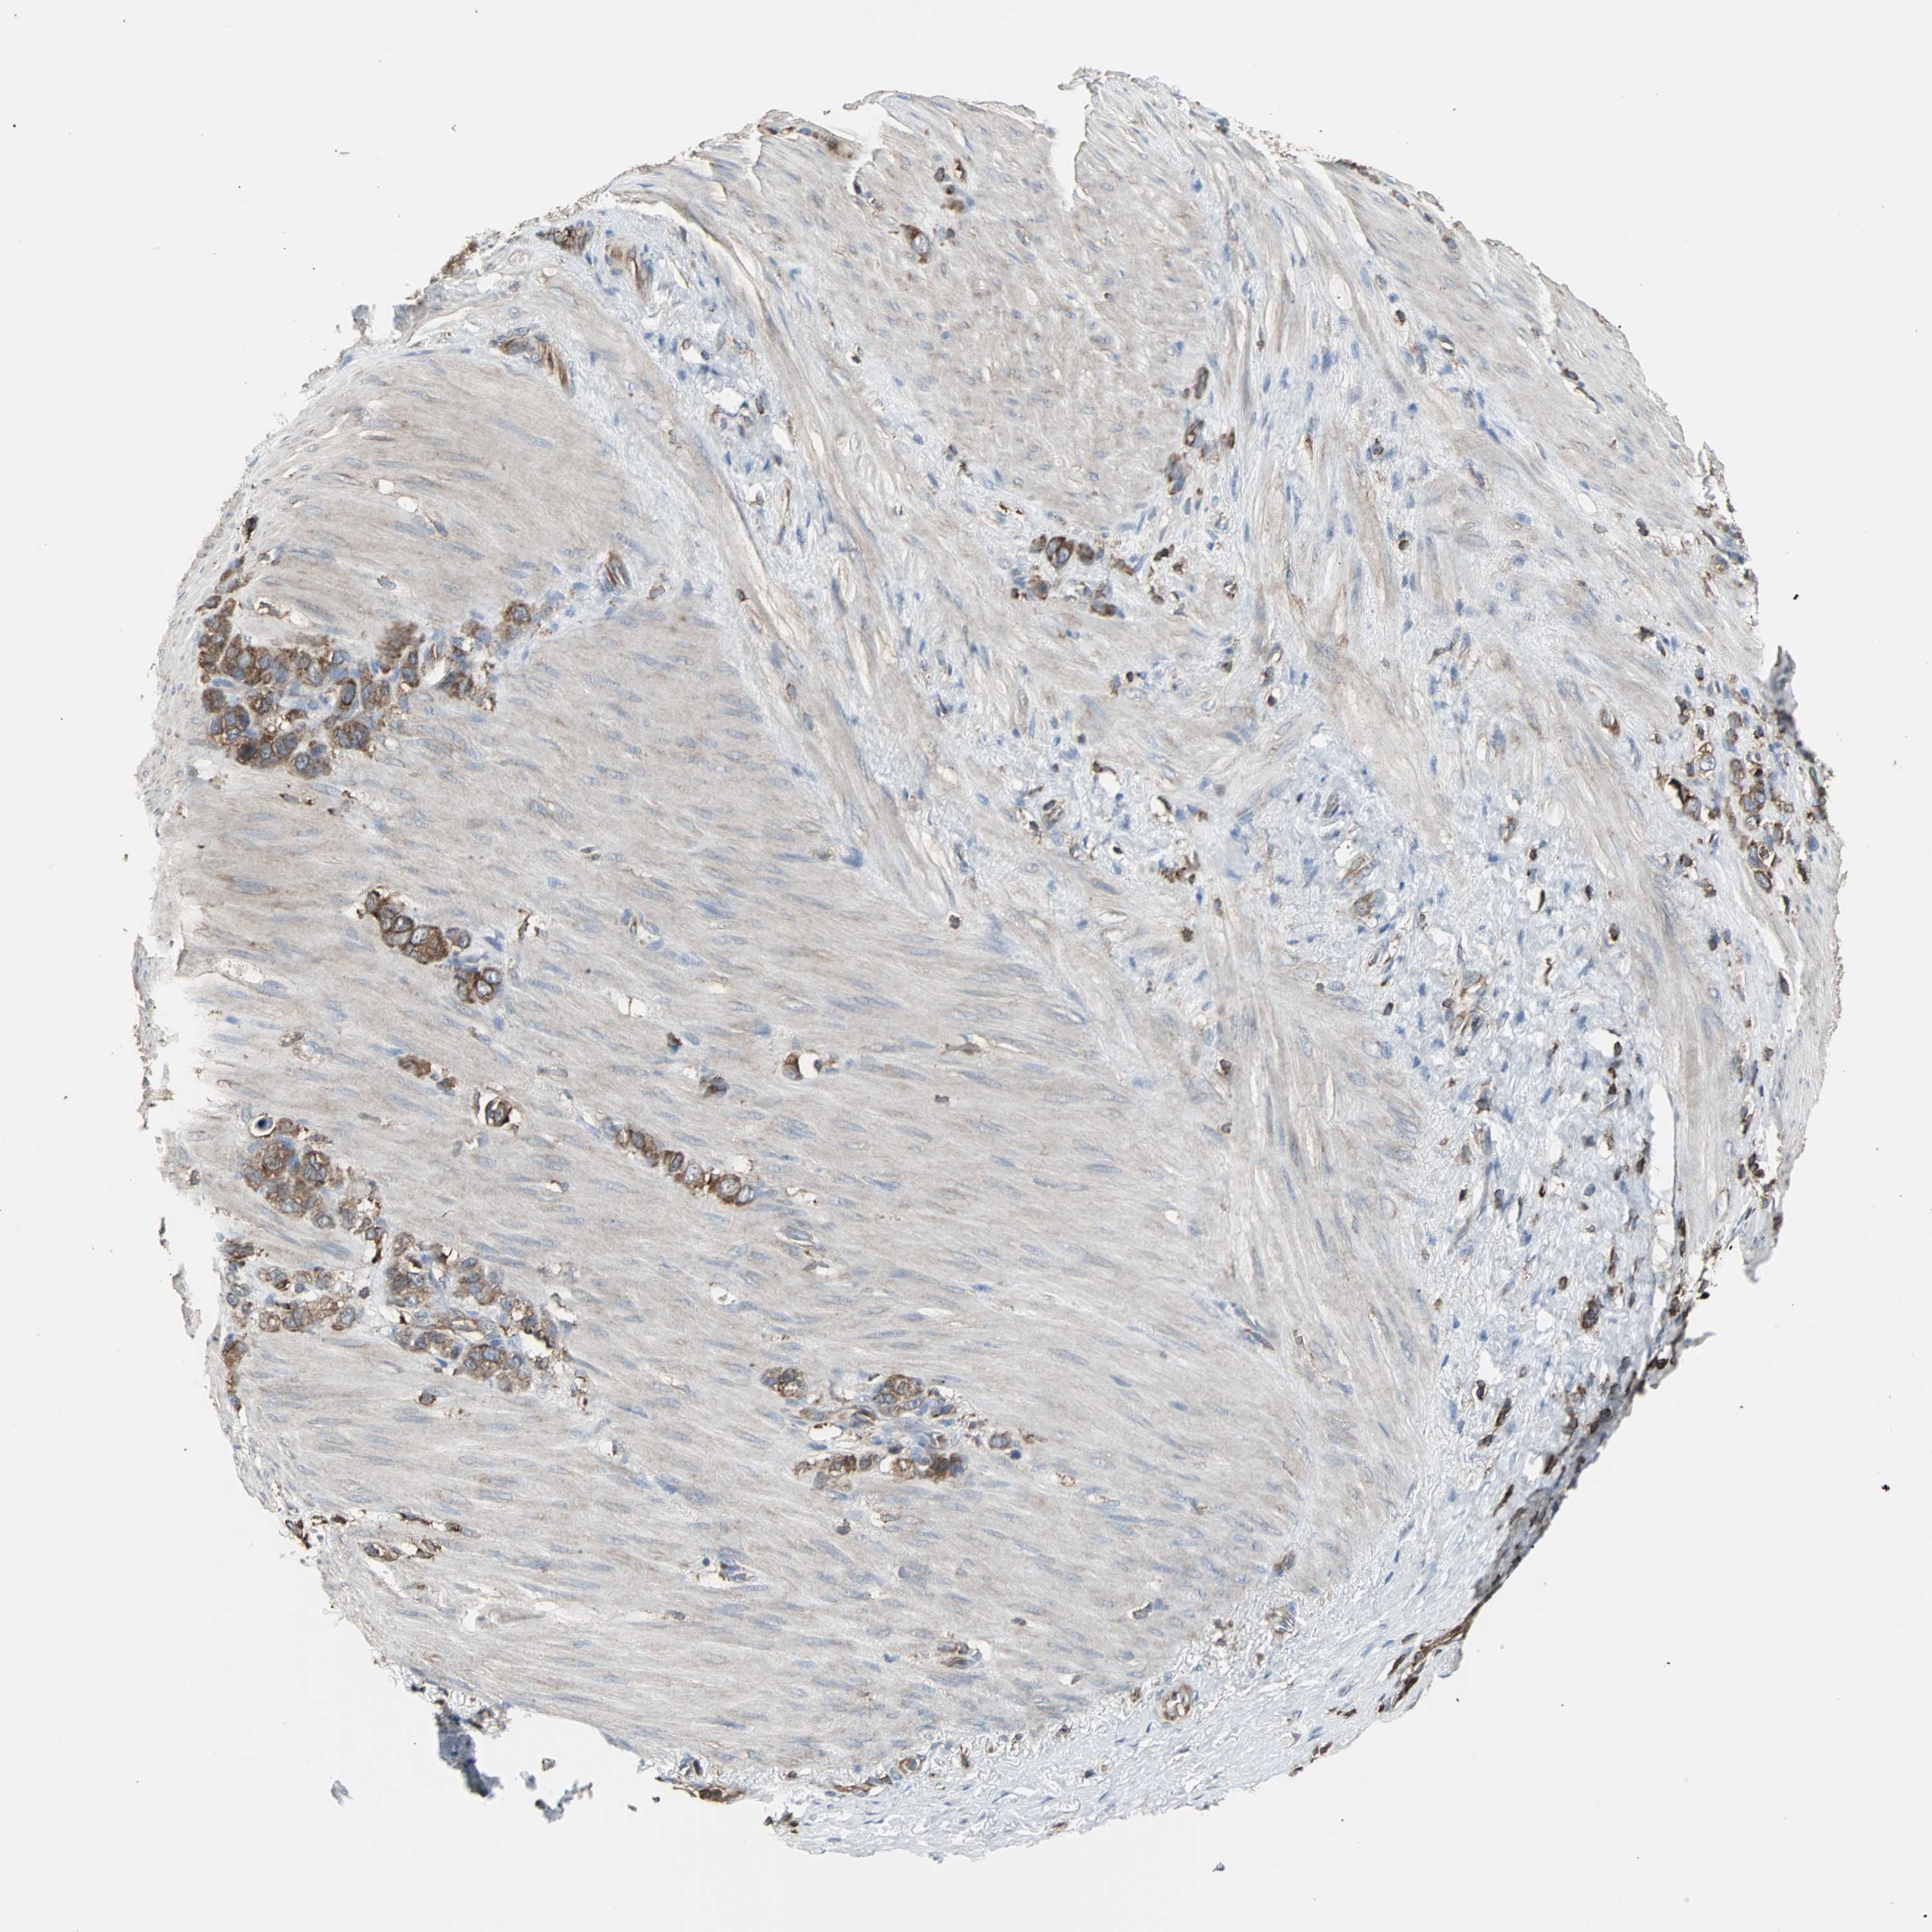

STOMACH CANCER - Protein expressioni

A mouse-over function shows sample information and annotation data. Click on an image to view it in a full screen mode. Samples can be filtered based on level of antibody staining by selecting one or several of the following categories: high, medium, low and not detected. The assay and annotation is described here.

Note that samples used for immunohistochemistry by the Human Protein Atlas do not correspond to samples in the TCGA dataset.

Antibody stainingi

Antibody staining in the annotated cell types in the current human tissue is reported as not detected, low, medium, or high, based on conventional immunohistochemistry profiling in selected tissues. This score is based on the combination of the staining intensity and fraction of stained cells.

Each image is clickable and will lead to virtual microscopy that enables deeper exploration of all samples and also displays staining intensity scores, fraction scores and subcellular localization as well as patient and tissue information for each sample.

Antibody HPA006979

Staining

High

Medium

Low

Not detected

Intensity

Strong

Moderate

Weak

Negative

Quantity

>75%

75%-25%

<25%

None

Location

Nuclear

Cytoplasmic/membranous

Cytoplasmic/membranous,nuclear

Adenocarcinoma, NOS

Adenocarcinoma, High grade